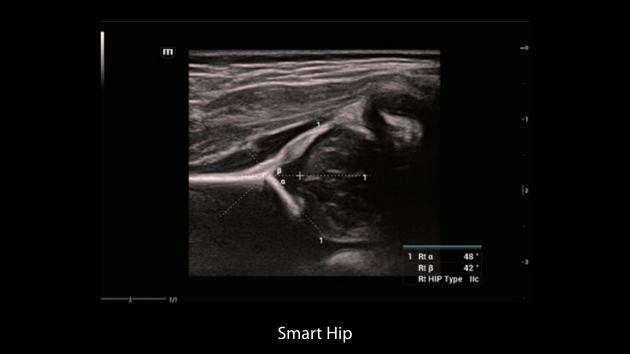

Obrazy kliniczne